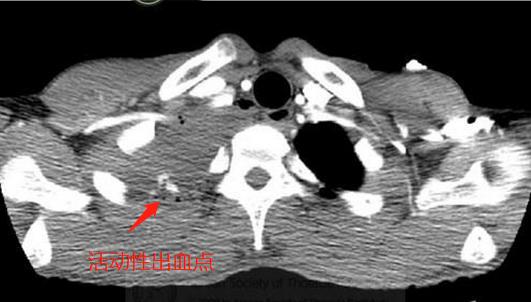

病人生命体征不稳,要警惕失血性休克,先找到出血点,马上急诊增强CT:

增强扫描发现右肺尖背侧造影剂渗漏,符合活动性出血,需要手术!